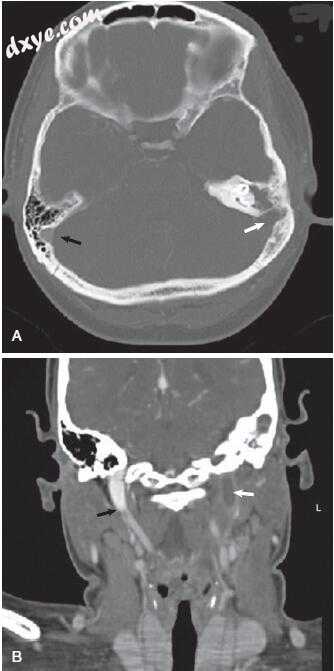

图-7. 颞骨骨扫描计算机断层扫描与Bezold脓肿患者的对比。 A,外耳道和中耳的不透明(白色箭头)。 还要注意乳突下部(黑箭头)的骨质破坏。 B,在茎突的根部(白色箭头)水平切割得更差,表明乳突尖端前部(黑箭头)的骨头破坏。 C,软组织开窗显示Bezold脓肿,在乳突尖端水平增强囊(箭头)。 D,可见脓腔(箭头)在颈部向下延伸至舌骨水平(箭头)。